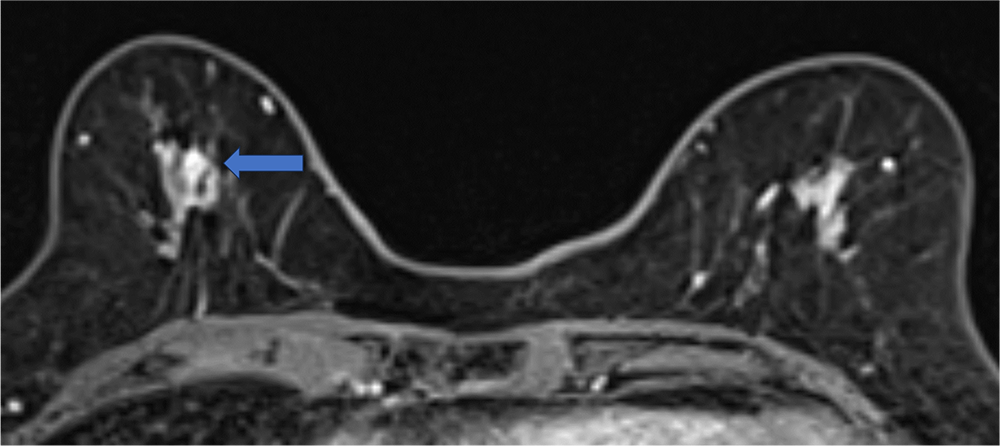

4. ダイナミックMRI 造影前 早期相 遅延相

病変は扁平な形状で均一に増強される。ダイナミックMRIの増強パターンはfast and plateauであった。

ダイナミックMRI 早期相

ダイナミックMRI 遅延相